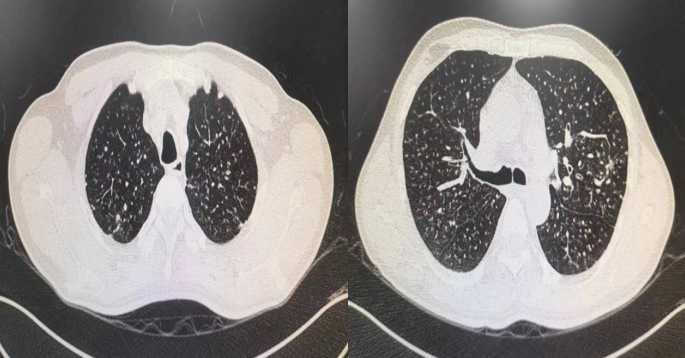

患者吴某,男性,45岁,因"反复咳嗽1年多,伴气喘3月余,五月中旬就诊南溪山医院呼吸与危重症医学科一区,入院查肺部 CT :1.两肺多发异常密度影,考虑职业相关性肺疾病,经追问病史,得知患者从事石头打磨工作多年,结合病史考虑患者肺部病变为尘肺可能性大。

图一 肺部CT